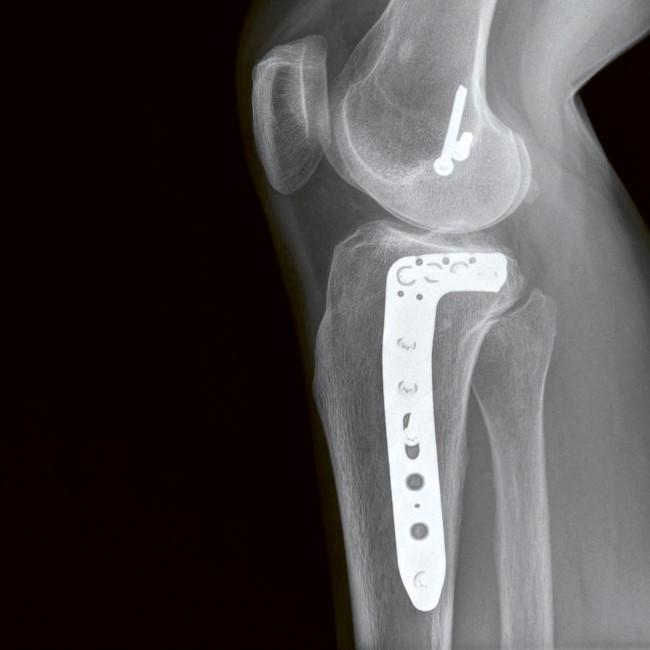

CLINICAL CASES: POYA CASE 2

We report a case involving a complex postero-lateral tibial plateau fracture with a particular involvement of the postero-latero-central fragment (PLC). The fracture was treated with a 6-hole POYA 3.5mm Lateral Proximal Tibia Plate.